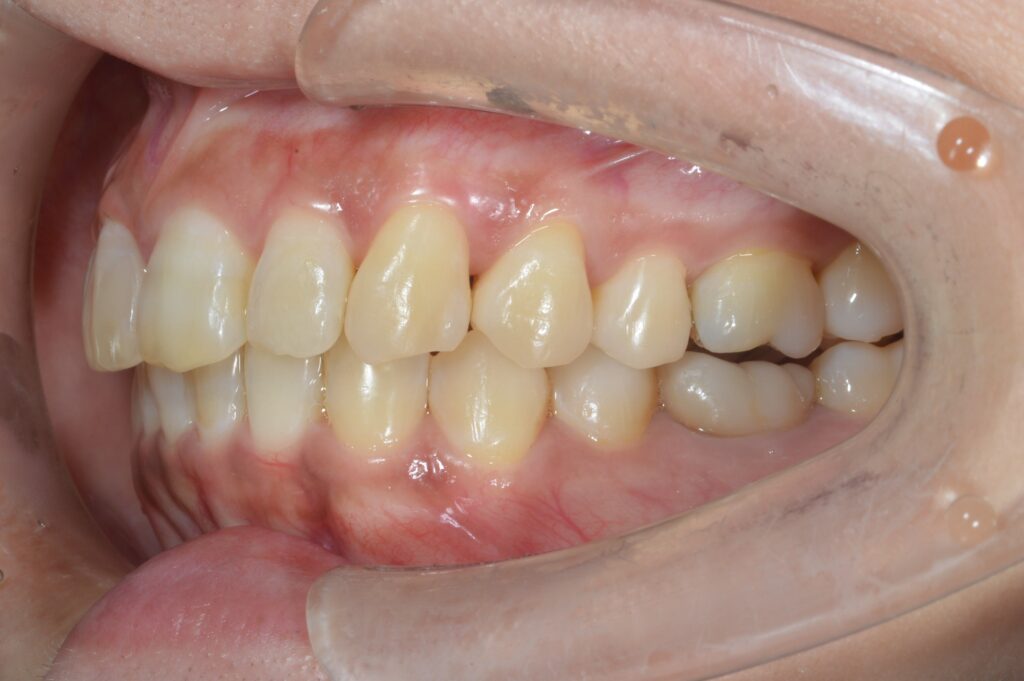

インビザライン(マウスピース矯正)にて上の前歯の重なりと下のデコボコを解消したケース

治療後

| 治療内容 | 上の前歯の重なりと、下のでこぼこの治療希望あり。インビザラインを用いて、矯正治療を行った。患者様はこちらの指示通り、確実にマウスピースを使用してくださった。微調整のため、追加アライナーの作成を2回行い、歯列が整ったので、保定に移行した。 |